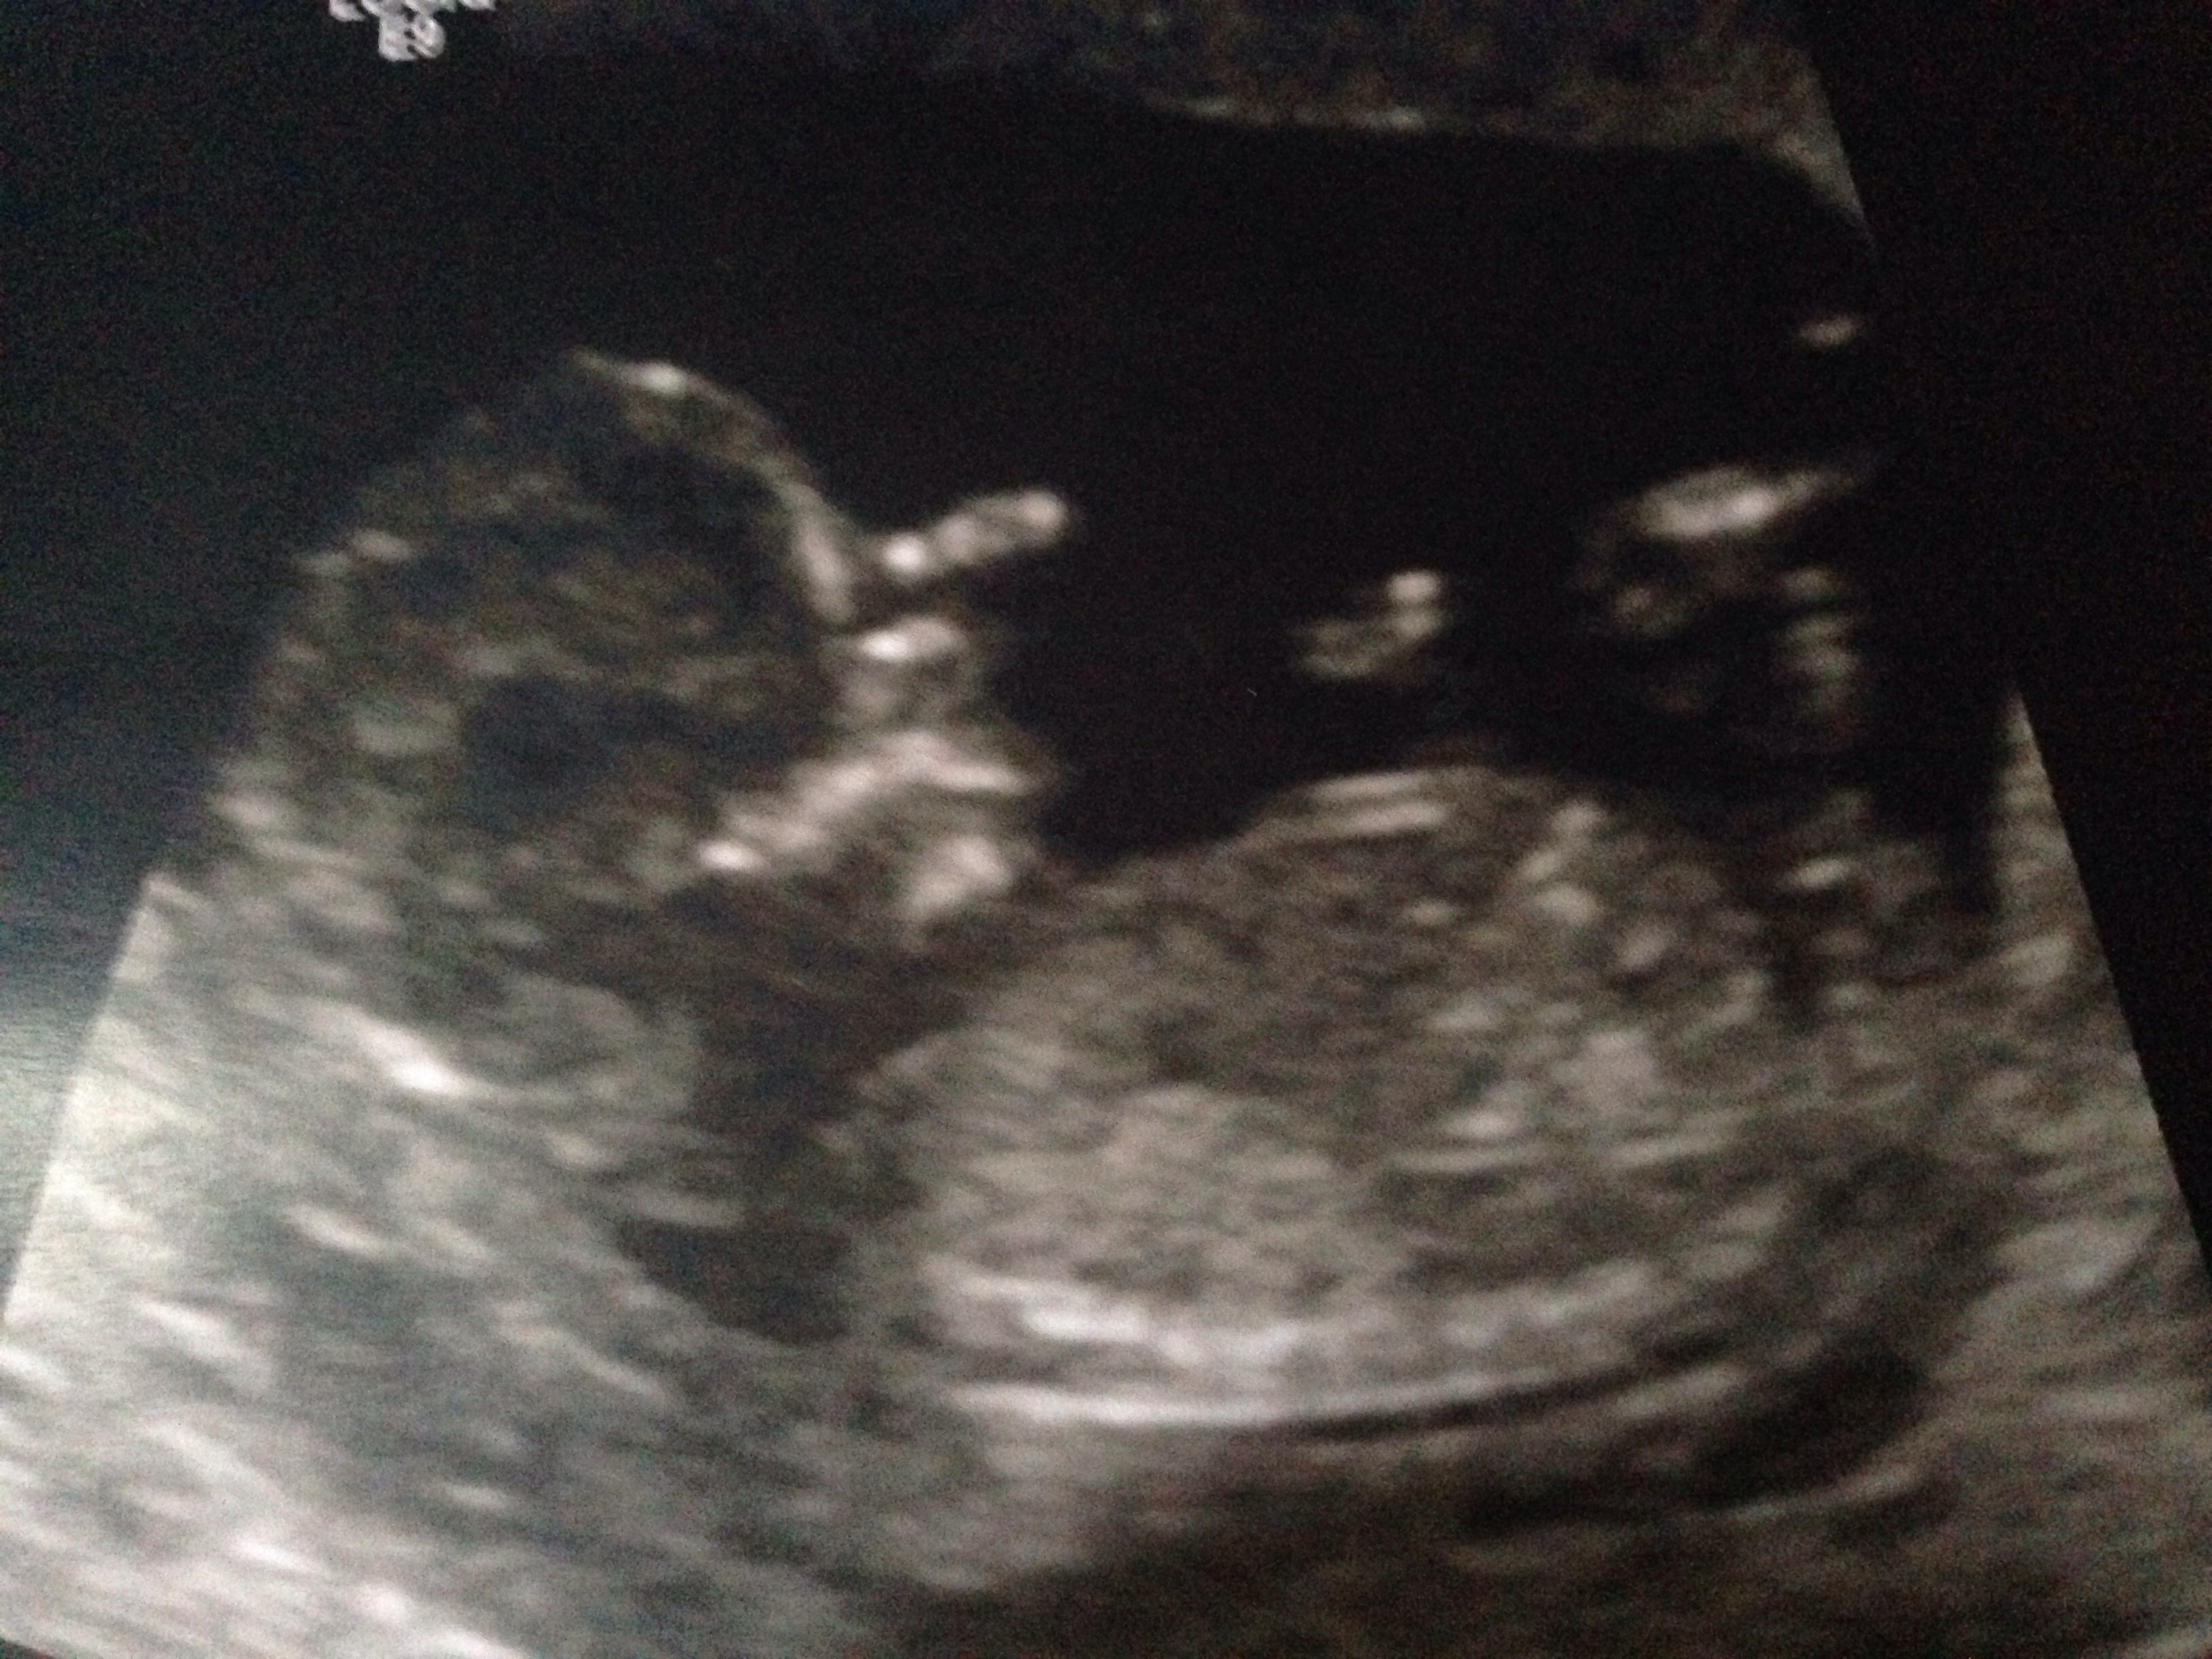

Hey I'm now 13 weeks 3 days these pics are from 13+1 can you predict gender I already have two boys looking at the nub I can't tellAttachment 16021Attachment 16022

No nub in top pic but I would say girl from the bottom pic :) congrats!

Boy skull but girlie nub!

Girl nub.